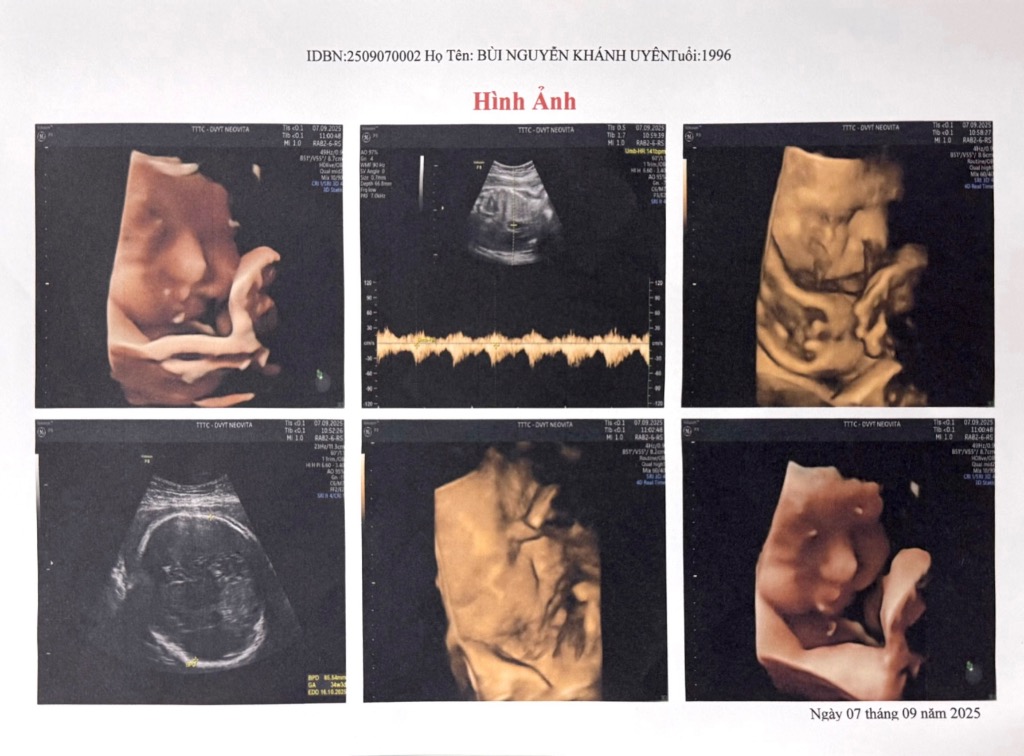

Bùi Nguyễn Khánh Uyên